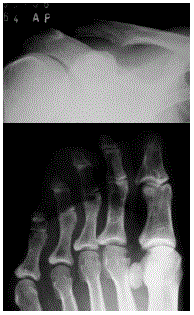

Criança levada a emergência por trauma na tíbia em jogo de futebol.

Baseado na imagem disponibilizada, qual o seu diagnóstico?